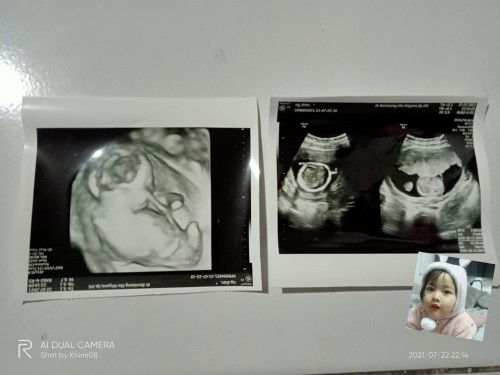

Bun mau tanya kemarin saya usg dan dokter nya bilang ini bb bayinya kecil 2,6 jadi belum bisa dilahirin padahal usg yg bulan kemarin HPL 30 Desember bb janin juga 2,6 kok kemarin bb masih masa dan HPL jadi mundur bulan Januari antara tgl 10-15 katanya karna bb janin masih kecil padahal saya sudah merasakan kontraksi palsu tapi belum pembukaan sama janin saya itu geraknya gak terlalu aktif kata dokter suruh hitung berapa tendangan bayi dalam sehari air ketuban saya juga masih kurang katanya kurang minum air dan kata dokternya nunggu 2-3 minggu lagi kalo masih bb kecil sama belum lahir mau di pacu ini sudah di kasi obat biar bb janin besar sama saya minum ice cream menurut bunda" saya harus gimana bun jangan di bully ya bun ππ» #seriusnanya #bantusharing